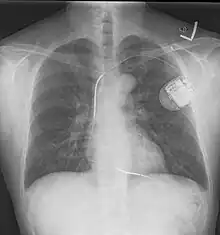

- A chest film after insertion of an implantable cardioverter-defibrillator, showing the shock generator in the upper left chest and the electrical lead inside the right heart. Note both radio-opaque coils along the device lead.